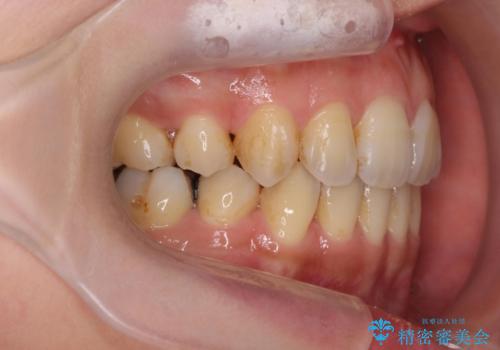

八重歯を矯正治療で治したい!

- 八重歯・がたつきのある歯並びの改善を求めて来院されました。

全部の歯が入り切るスペースがなかったため、小臼歯4本を抜去しワイヤーを用いたマルチブラケット矯正を選択しました。

歯並びの改善と共に、歯ブラシがしやすくなった!と喜んでいただくことができました。